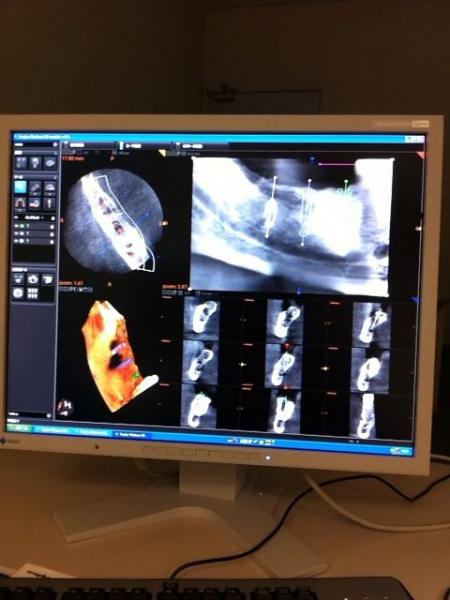

かなもり歯科クリニックではインプラントの処置の前には歯科用CTにて診断し

安全、確実な治療を心がけております。

お気軽にご相談下さい。